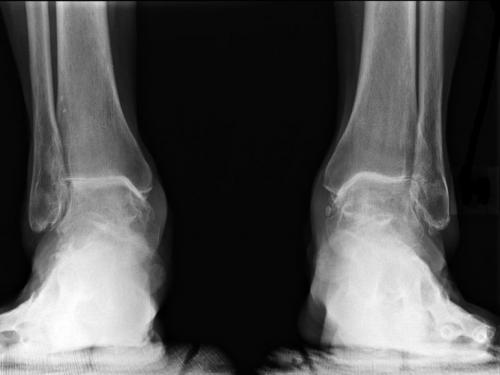

Артроз правого голеностопного сустава. Лечение посттравматического артроза голеностопного сустава

Посттравматический артроз голеностопного сустава — это дегенеративно-дистрофическое разрушение, которое появляется в результате травмирования голеностопа. Патология характеризуется хроническим прохождением. Обычно она развивается постепенно, регулярно проявляя себя интенсивными болями. Своевременное лечение заболевания и умеренные нагрузки смогут помочь сдержать прогрессирование артроза.

Основные стадии

Этот недуг развивается постепенно. С учетом усугубления дегенеративных процессов отмечается все более выраженное появление соответствующей симптоматики.

С учетом уровня разрушения и выраженности заболевание условно делят на три этапа:

- На первом этапе посттравматического артроза на определенных участках поверхностей суставов истончается костная ткань. Трение во время ходьбы приводит к регулярному появлению болевого синдрома и чувства дискомфорта. После отдыха эта симптоматика исчезает. Первую стадию заболевания можно вылечить в домашних условиях. В этом случае важно снизить нагрузки, к примеру, отказ от каблуков, сброс лишнего веса. Чаще всего диагноз установить не получается, поскольку патологические процессы в голеностопном суставе не отображаются во время обследования на УЗИ или на рентгеновском снимке.

- На втором этапе обнаженная хрящевая ткань на разрушенном суставе начинает увеличиваться в объеме. Это защитная реакция в ответ на повышение нагрузок. Увеличенная в размерах ткань начинает травмировать близлежащие здоровые участки, провоцируя последующую дегенерацию суставов. Болевые ощущения проявляются все чаще, могут отмечаться даже ночью.

- Третий этап характеризуется атрофией связочного аппарата, суставной ткани, деформацией и истончением хрящей.